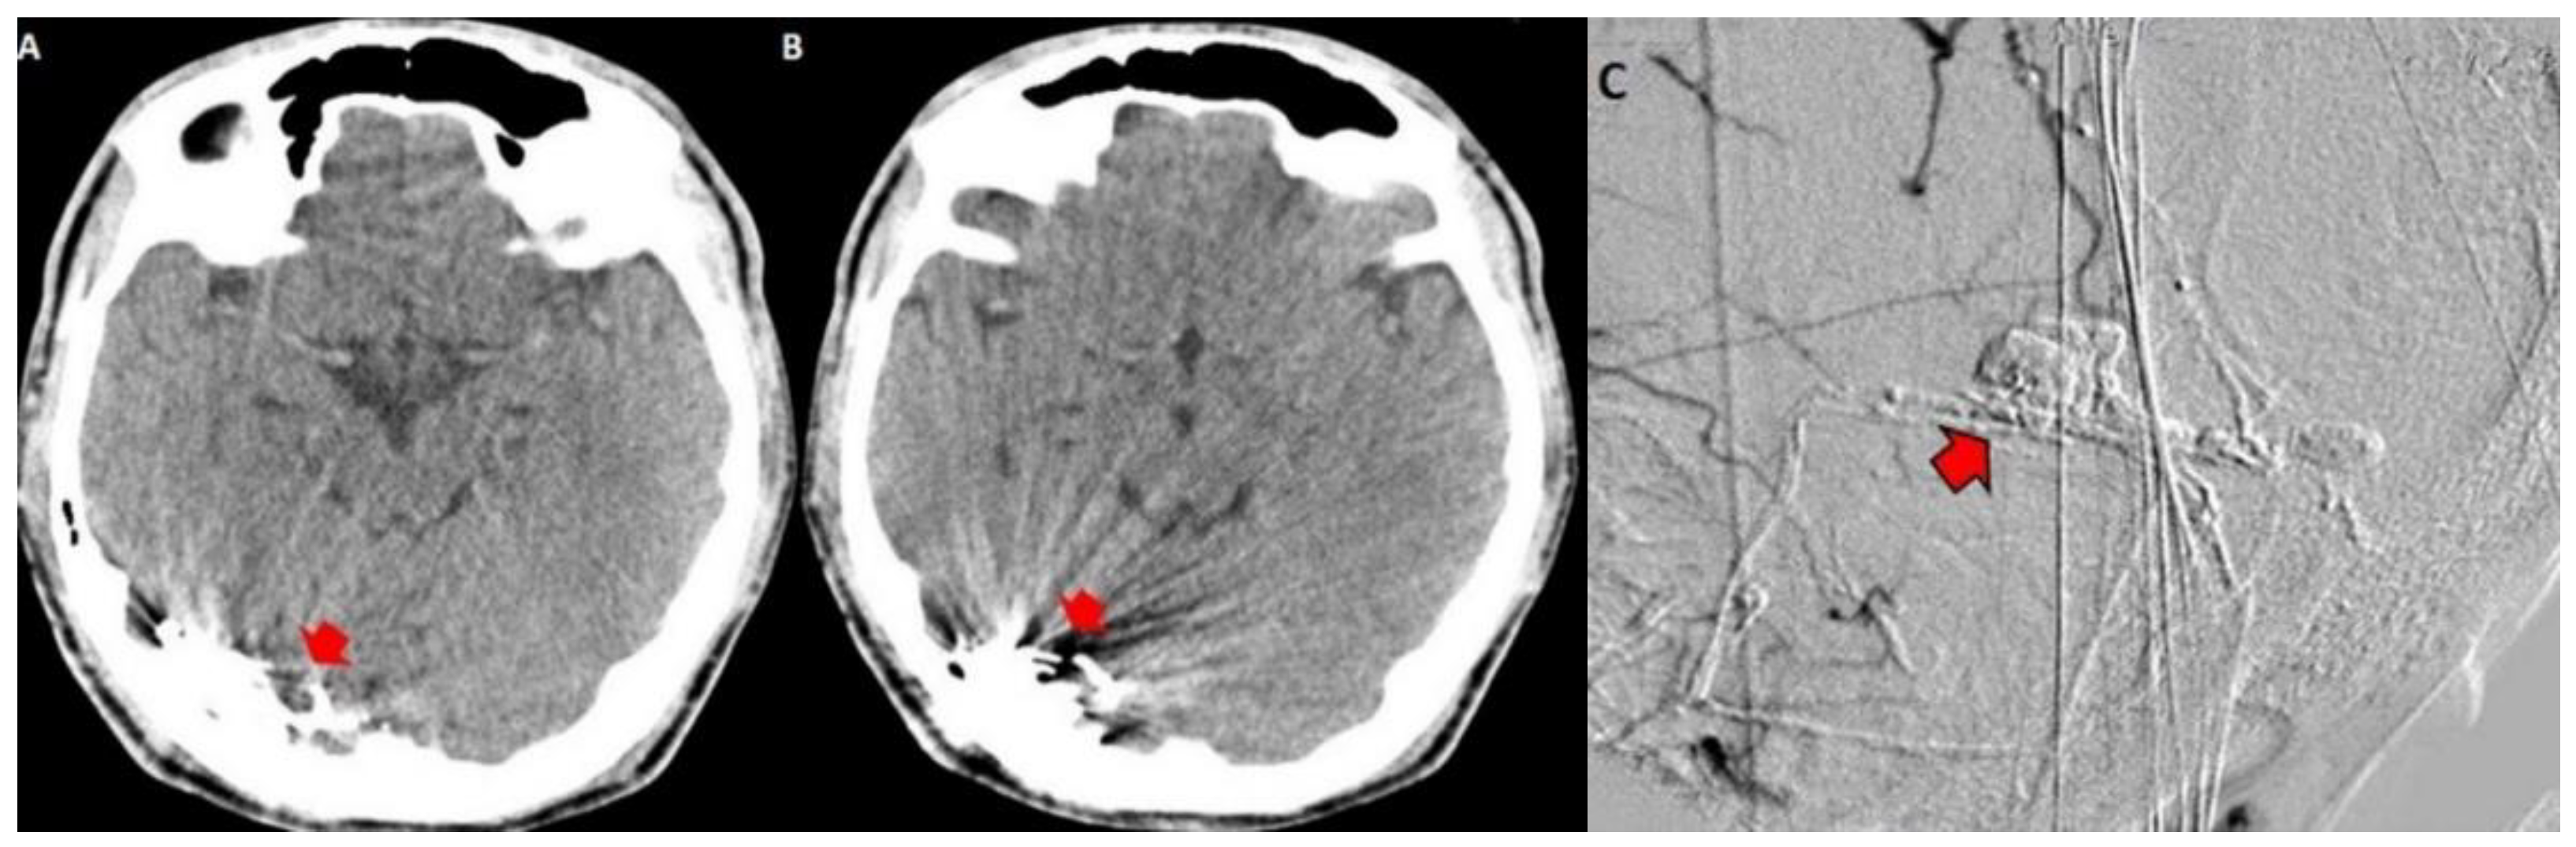

Figure 6.

Contrasted CT showing embolized dural arteriovenous fistula with Onyx by endovascular procedure. This material produces artifacts with image distortion in the right occipital region (red arrow heads in (A,B)). The angiography after the therapeutic procedure of the fistula shows that it was successfully embolized, so it is not contrasted (red arrow with black outline in (C)).